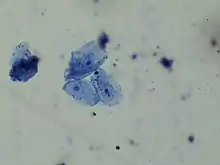

Histology

In staining during microscopic examination for diagnosis or research, acid dyes are used to color basic tissue proteins. In contrast, basic dyes are used to stain cell nuclei and some other acidic components of tissues.[8] Regarding cellular structures, acid dyes will stain acidophilic structures that have a net positive charge due to the fact that they have a negatively charged chromophore. Acidophilic structures include the cytoplasm, collagen and mitochondria. The two have an affinity for each other due to the conflicting charges.[9][10] Examples of acid dyes used in medicine include:[11]